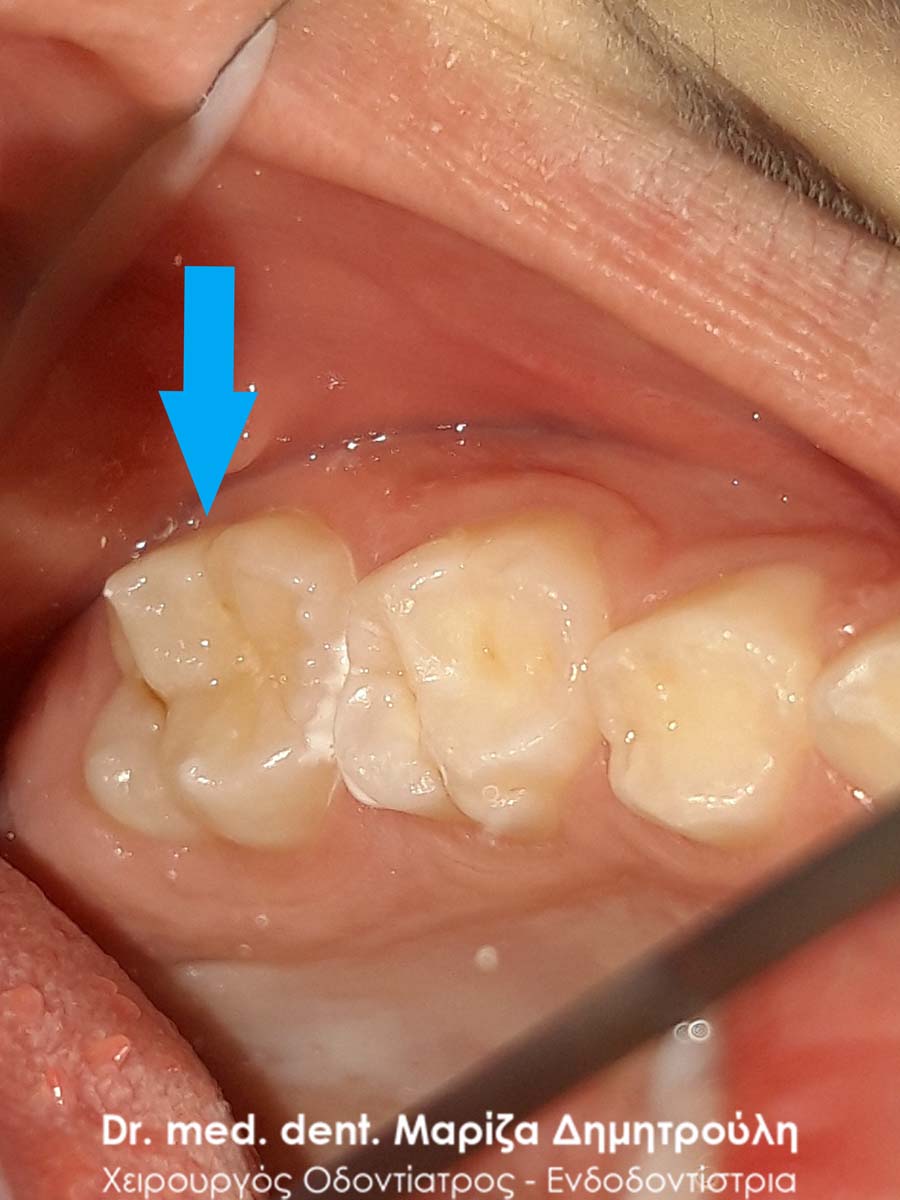

Περιστατικό – Sealant / προληπτική κάλυψη οπών και σχισμών

Στην έφηβη αυτή μικρή κυρία πραγματοποιήθηκε προληπτική κάλυψη της μασητικής επιφάνειας του μόνιμου άνω πρώτου γομφίου, για την προστασία του δοντιού από την τερηδόνα. Εφόσον η μασητική επιφάνεια ενός δοντιού καλύπτεται με υλικό sealant μειώνεται ο κίνδυνος προσβολής από τερηδονογόνα μικρόβια, καθώς συγκεντρώνονται λιγότερα μικρόβια και υπολείμματα τροφών στη μασητική επιφάνεια ενώ παράλληλα το παιδί μπορεί να βουρτσίζει πιο αποτελεσματικά και εύκολα. Ο χρόνος ζωής ενός sealant κυμαίνεται από 2 – 5 χρόνια.

ΠΡΙΝ